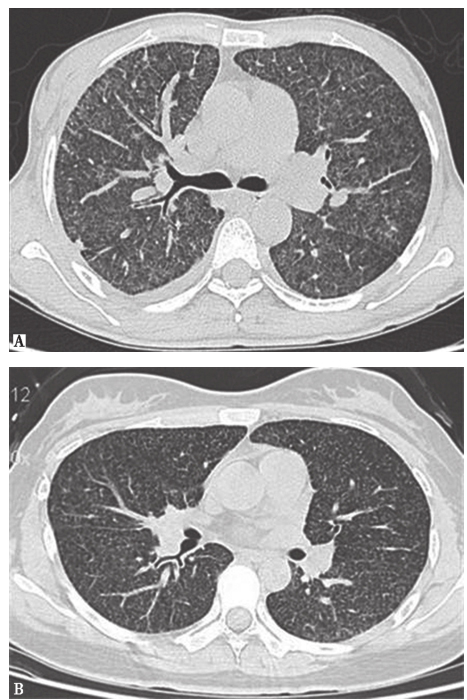

患者CT主要表现为两肺磨玻璃影、多发小结节影,局部可见网状影及牵拉性支气管扩张。首先须排查风湿免疫病和肿瘤。风湿免疫病是一种系统性疾病,往往伴有肾、关节、皮肤、肌肉和血液等多系统损伤,单一累及肺组织者少见。本例患者无发热,无皮疹或关节痛,无明显口干、眼干,无反复口腔溃疡等,患风湿免疫病可能性不大,可进一步完善自身免疫相关检查以排除。肿瘤方面的鉴别诊断,主要应排查肺转移癌。血源性转移癌可出现随机分布的结节,一般两肺对称,广泛分布于肺的各个部位,结节密度较高,边缘一般较清楚(图3)。淋巴转移癌表现为支气管血管束不规则结节状增厚,小叶间隔增厚呈串珠状或胸膜下多角形细线结构,可伴有患侧胸腔积液 (图4)。患者常有刺激性咳嗽。本例患者肺内无原发癌表现,临床症状、体征亦无其他部位肿瘤提示,发生肺转移癌可能性较小。

图3肺癌伴肺内转移CT表现

女性患者,45岁,肺癌伴肺内转移。胸部CT见两肺广泛粟粒状小结节影

图4癌性淋巴管炎胸部CT表现

女性患者,55岁,胃癌。胸部CT可见双侧少量胸腔积液伴网格状周边型结节,呈癌性淋巴管炎表现